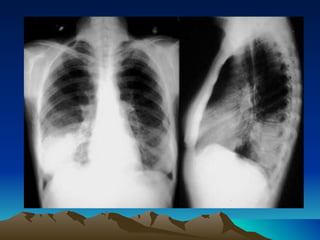

NAC-Diagnostico Cuadro clinico (F, DT, D, T, E) Exploracion fisica (S. Consolidacion) Radiografia de torax: Patron alveolar:  neumonia alveolar, lobar, basal o segmentaria. Opacidad homogenea con broncograma aereo.  Neumonia neumococica.  Cualquier neumonia bacteriana. Patron de bronconeumonia:  neumonia bronconeumonica. Imagenes radiologicas de focos multiples en ambos campos pulmonares.  Neumonia estafilococica, enterobacterias.  Por via hematogena. Patron intersticial:  disociacion clinico-radiologico, neumonias atipicas.  M. Pneumoniae, Clamidias y virus.

NAC-Diagnostico Cuadro clinico(F, DT, D, T, E) Exploracion fisica (S. Consolidacion) Radiografia de torax: Patron alveolar: neumonia alveolar, lobar, basal o segmentaria. Opacidad homogenea con broncograma aereo. Neumonia neumococica. Cualquier neumonia bacteriana. Patron de bronconeumonia: neumonia bronconeumonica. Imagenes radiologicas de focos multiples en ambos campos pulmonares. Neumonia estafilococica, enterobacterias. Por via hematogena. Patron intersticial: disociacion clinico-radiologico, neumonias atipicas. M. Pneumoniae, Clamidias y virus.